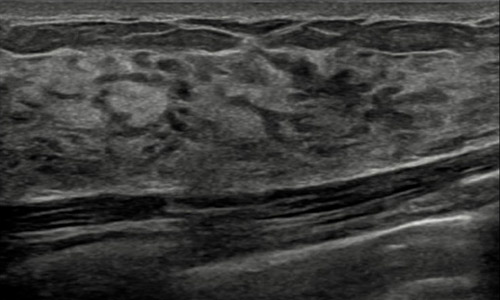

Cómo se ve el tejido mamario en una ecografía

- Permite distinguir entre un nódulo sólido y uno de contenido líquido (quiste) y mejora la caracterización los nódulos sólidos (como complemento de la mamografía).